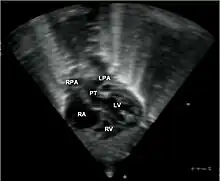

Echocardiogram in transposition of the great arteries. This subcostal view shows the left ventricle giving rise to a vessel that bifurcates, which is thus identified as the pulmonary artery.

Abbreviations: RA=right atrium, RV=right ventricle, LV=left ventricle, PT=pulmonary trunk, LPA and RPA=left and right pulmonary artery.